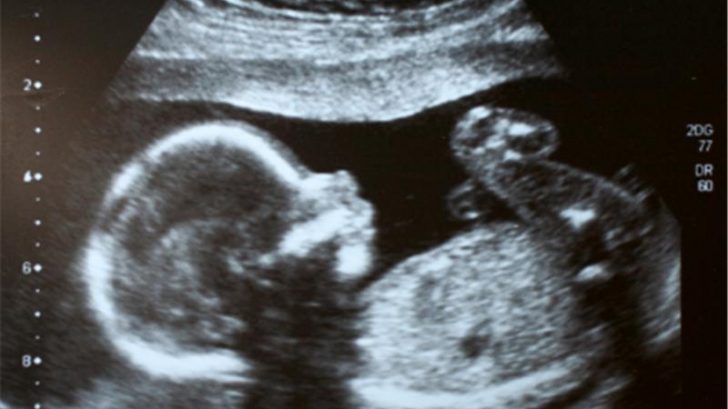

Jakými stadii embryo prochází, než dojde k jeho přenosu do dělohy?

- Zygota – vzniká oplozením vajíčka spermií, je to buňka s kompletní chromozomální výbavou.

- Blastomera – dvou- až šestnáctibuněčné embryo. Embryo se do této fáze dostane zhruba po čtyřiceti hodinách od vzniku zygoty, všechna další dělení buněk (rýhování) probíhají v kratším časovém intervalu. Třetí den je embryo stále ve stadiu blastomery, může obsahovat až šestnáct buněk a za optimálních okolností je připraveno k transferu.

- Morula, kompaktní morula – čtvrtý den – buňky jsou už nepočitatelné, na povrchu embrya jsou patrné rýhy rýhování – odtud fáze dostala název. Embryo má pod mikroskopem vzhled plodu moruše – latinsky morula.

- Blastocysta – pátý den, počet buněk už nelze spočítat, můžeme pozorovat dvě skupiny buněk, které dělíme na embryoblast – buněčná masa, ze které vznikne plod a trofoblast – oblast, ze které vznikne placenta. Tuto oblast buněk je možné využít pro preimplantační genetickou diagnostiku (PGD) a preimplantační genetický screening (PGS).